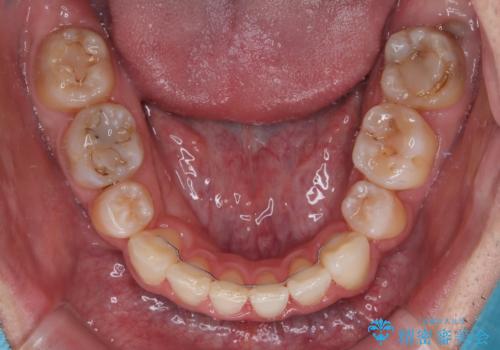

顎が左右にずれた咬み合わせ ハーフリンガルの抜歯矯正

- 口元の突出感を気にして来院された患者様です。

目立たない装置を希望され、上顎が裏側装置で下顎が表側装置のハーフリンガルを希望されました。

上下の顎骨が左右に大きくずれており、奥歯が交叉咬合となっていたため、ハーフリンガルよりも表側装置をおすすめしましたが、目立たない装置を強く希望されたため、治療期間が長期化することを前提に、ハーフリンガルにて抜歯矯正を行うこととしました。